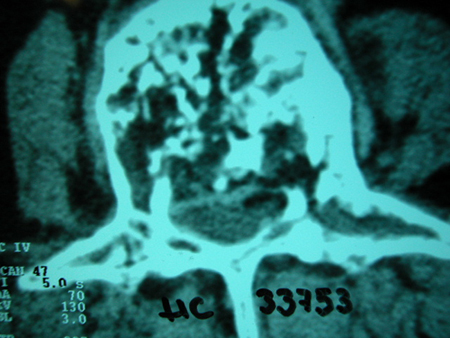

TC exostosis occipital congénica.

TC exostosis occipital congénita.